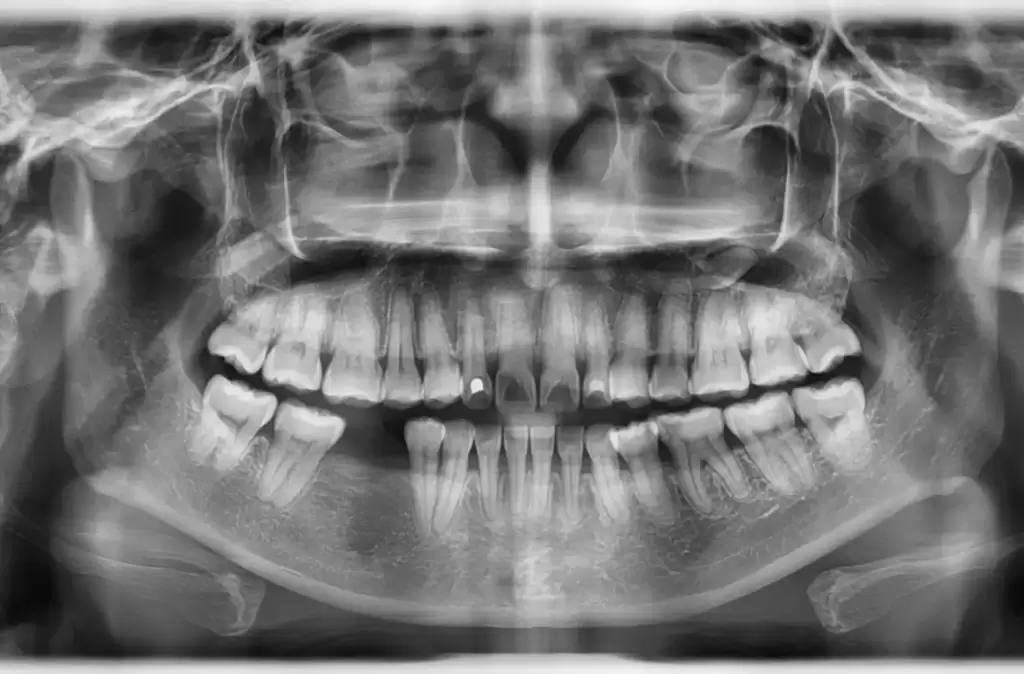

Dental implants replicate the structure of natural tooth roots. Each implant consists of a small titanium post surgically placed into the jawbone. Over the next few months, the bone grows and fuses around the post in a process called osseointegration.

This fusion allows the implant to function just like a natural root, delivering the same kind of mechanical stimulation needed to maintain bone density. As a result, implants effectively halt bone loss and help preserve the strength and volume of the jaw.